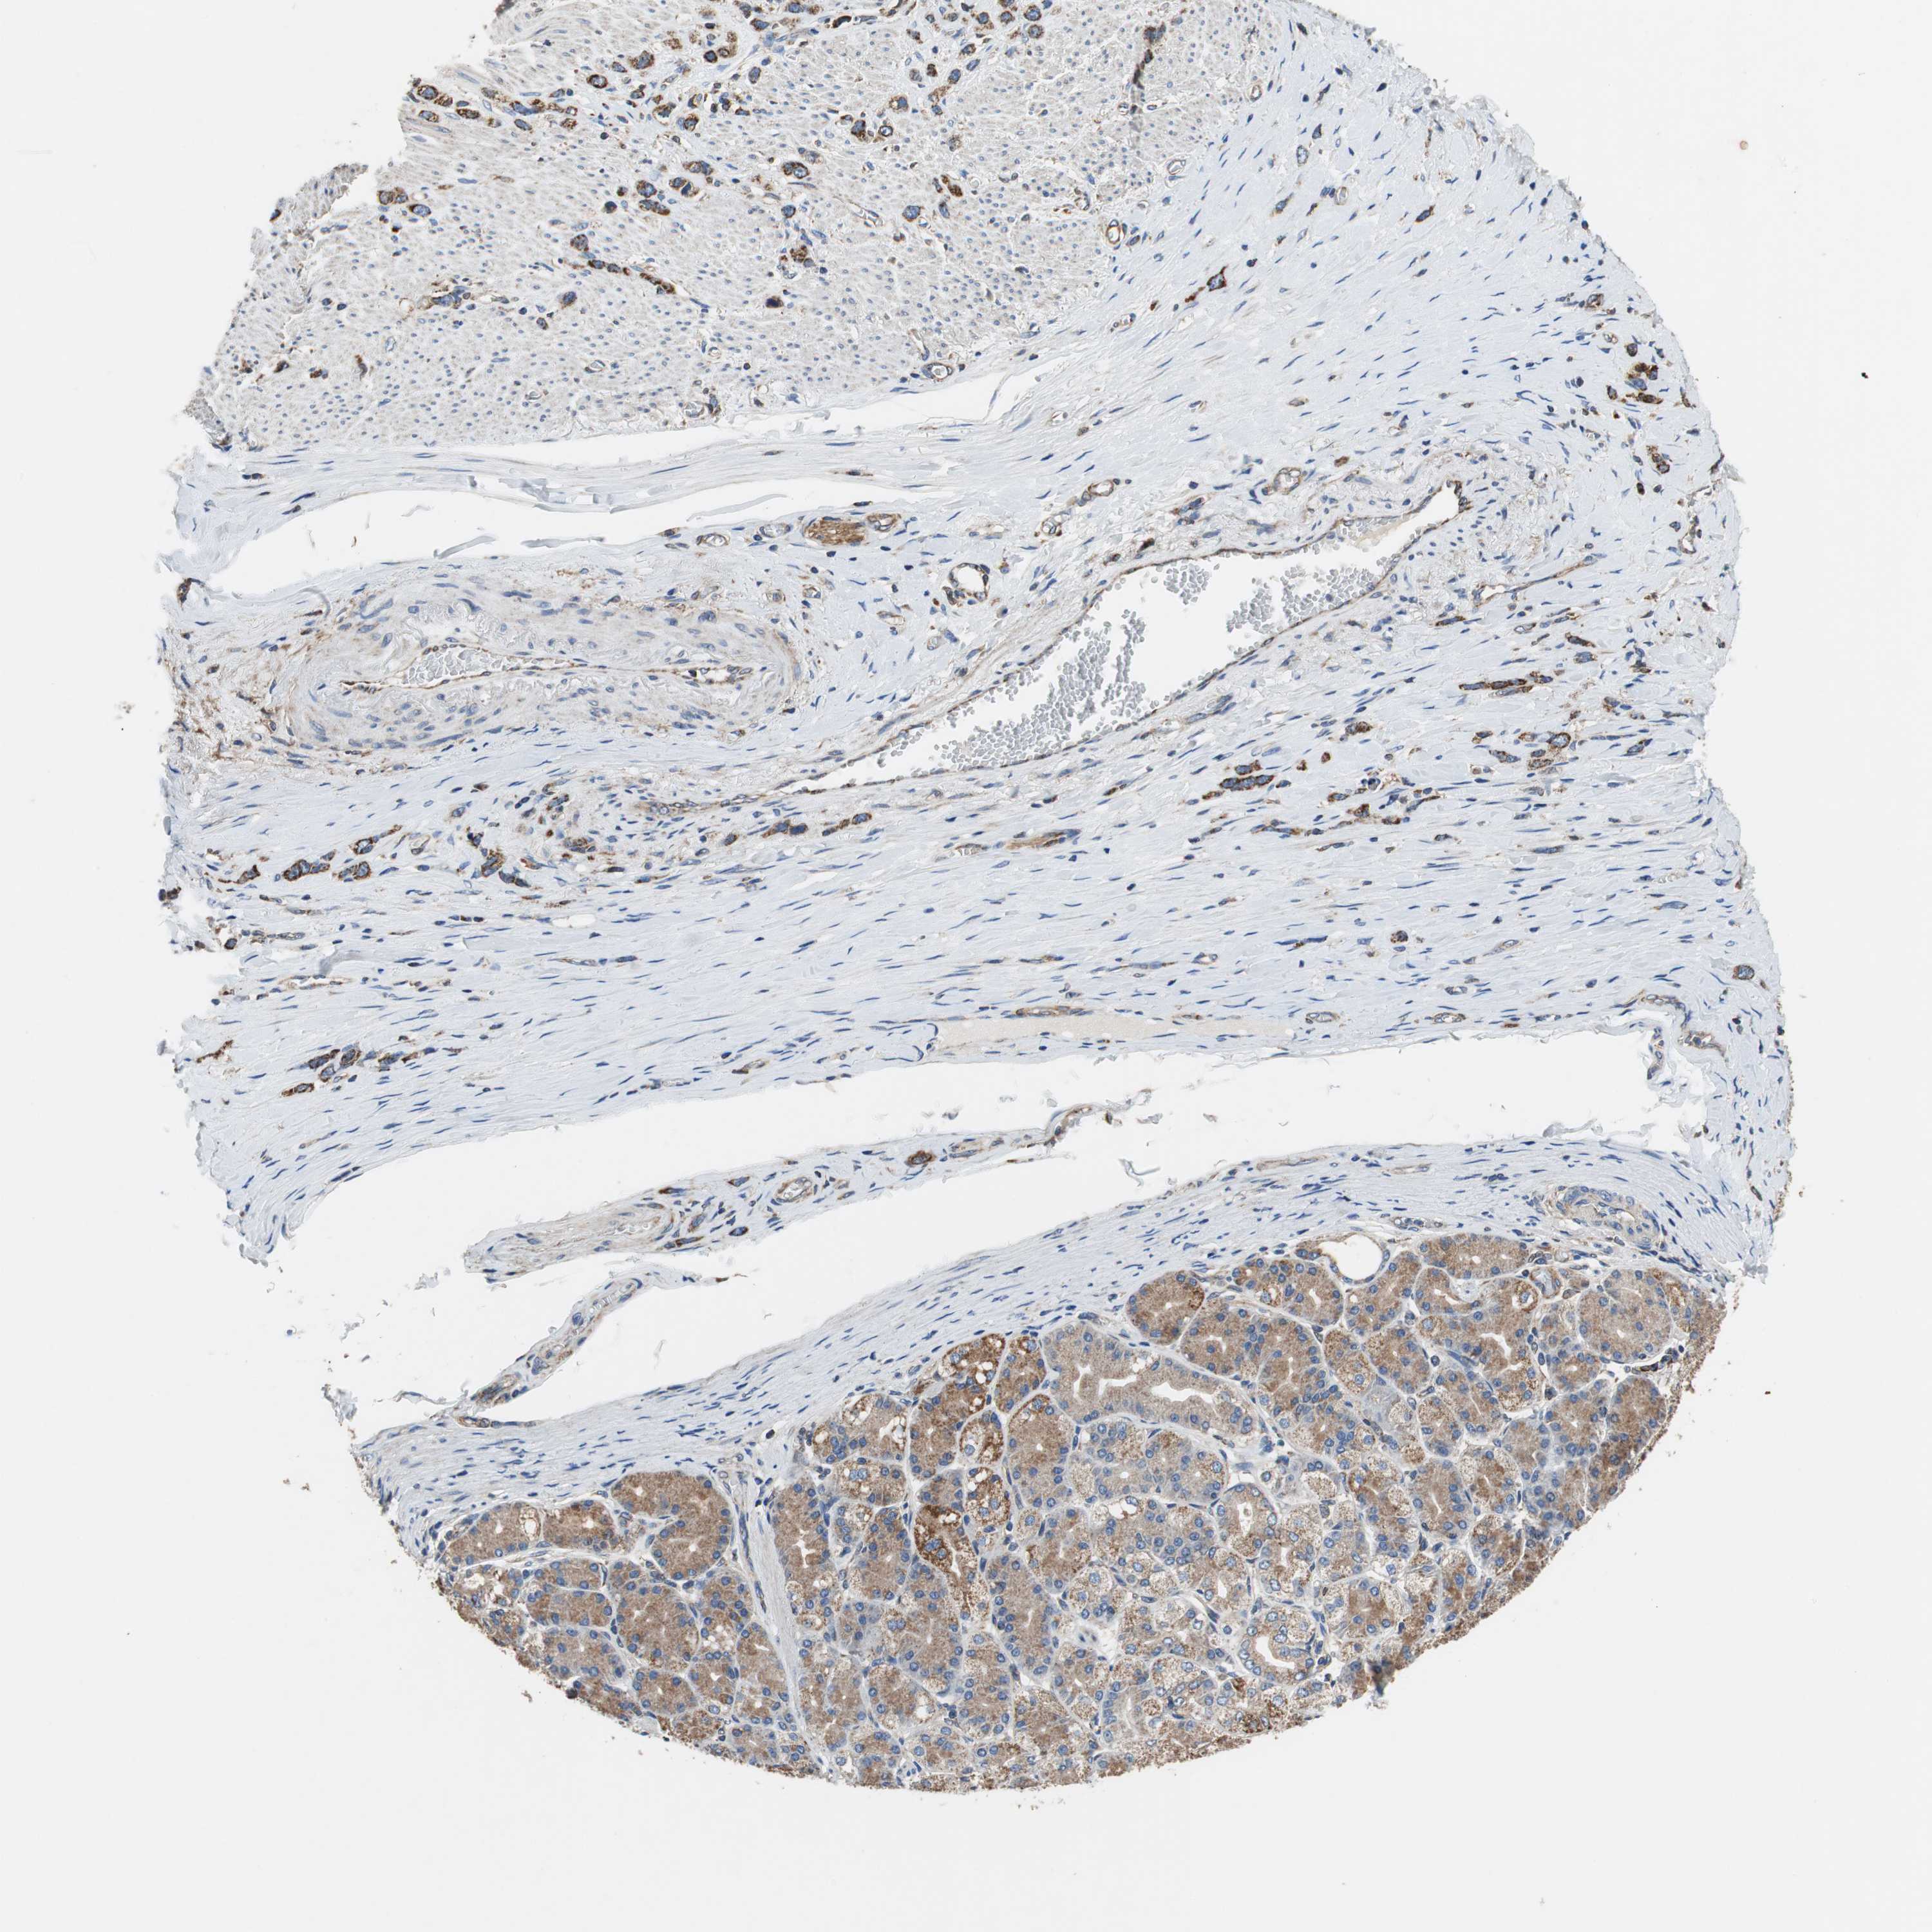

STOMACH CANCER - Protein expressioni

A mouse-over function shows sample information and annotation data. Click on an image to view it in a full screen mode. Samples can be filtered based on level of antibody staining by selecting one or several of the following categories: high, medium, low and not detected. The assay and annotation is described here.

Note that samples used for immunohistochemistry by the Human Protein Atlas do not correspond to samples in the TCGA dataset.

Antibody stainingi

Antibody staining in the annotated cell types in the current human tissue is reported as not detected, low, medium, or high, based on conventional immunohistochemistry profiling in selected tissues. This score is based on the combination of the staining intensity and fraction of stained cells.

Each image is clickable and will lead to virtual microscopy that enables deeper exploration of all samples and also displays staining intensity scores, fraction scores and subcellular localization as well as patient and tissue information for each sample.

Antibody HPA006311

Antibody HPA022904

Staining

High

Medium

Low

Not detected

Intensity

Strong

Moderate

Weak

Negative

Quantity

>75%

75%-25%

<25%

None

Location

Nuclear

Cytoplasmic/membranous

Cytoplasmic/membranous,nuclear

Adenocarcinoma, NOS

Adenocarcinoma, High grade